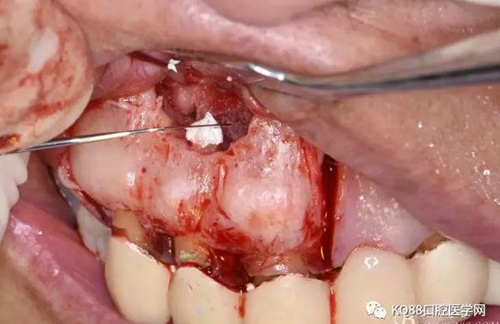

圖10.剝離囊壁

圖11.摘除囊壁后形成的骨腔

圖12.超生骨刀切除12根尖